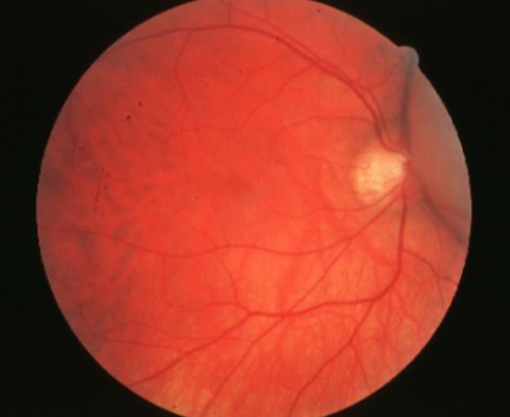

low

what is the concern for this being melanoma?

low

what is the concern for this being melanoma?

low

what is the concern for this being melanoma?

low

what is the concern for this being melanoma?